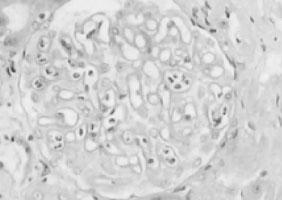

2.光镜检查 肾间质高度水肿,偶可见到肾静脉分支中有血栓形成,肾小球毛细血管扩张淤血,并可见节段性粒细胞浸润和微血栓形成。肾小管上皮细胞空泡变性,刷状缘脱落,而小动脉无明显病变(图5—7,图5—8)。慢性期,肾间质纤维化,肾小管萎缩,肾小球缺血。

图5—7 肾静脉血栓,肾小球毛细血管内粒细胞聚集